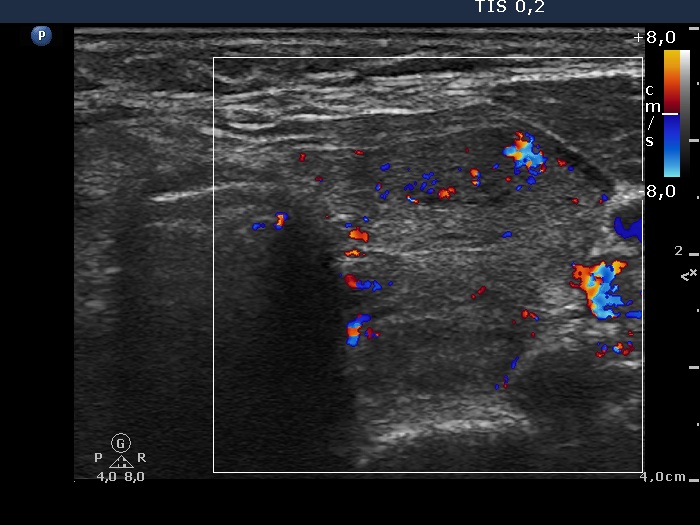

Consecutively operated patients with autoimmune thyroid disease - case 8 (409) (ultrasonographic picture 6)

Left lobe, transverse view, color Doppler mode. The lobe has an average vascularization.